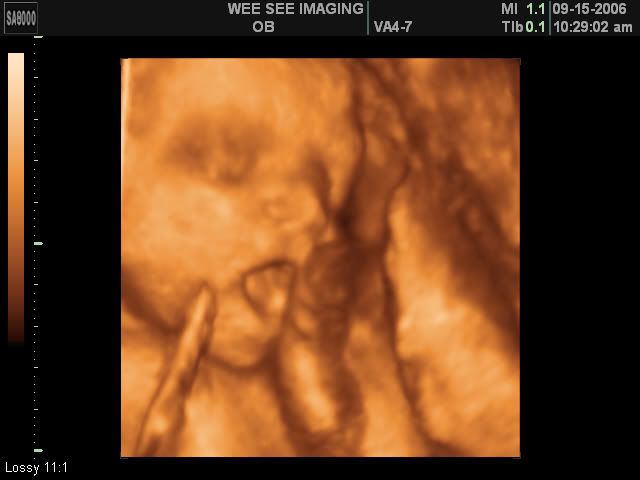

Victoria Rose Kelly

Date Due: December 15, 2006